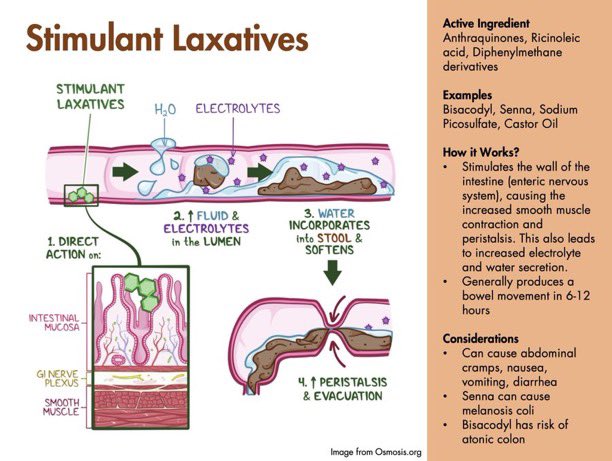

💩How laxatives work Remember BOSS for the 4 classes 💡🧠 #GIMnemonics B: Bulk-forming O: Osmotic S: Stool softeners S: Stimulant Key in #ICU & all medicine areas #MedEd #MedX #ICUNutrition #FOAMcc Enrik Aguila & Keith Siau